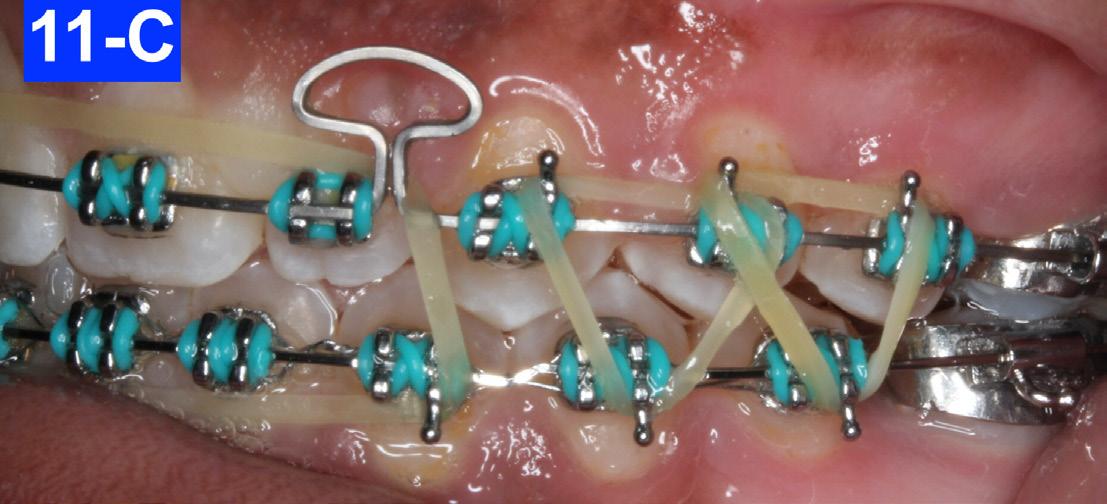

After twelve months of treatment, we inserted a Dr. Nanda Mushroom loop arch wire (019 x .025 CNA) in the maxilla to condense the spaces.7,8 The mushroom loop is opened 1.0 mm per month on both sides by pulling the arch wire back and placing a crisp bend back (cinch). It is advisable to heat treat and anneal the ends of the arch wire first. There was a .018 SS arch wire in the mandible. The patient continued with triangular and box elastics as previously (Figures 11-A, B, C).

Fig. 11-A: Mushroom AW, frontal view